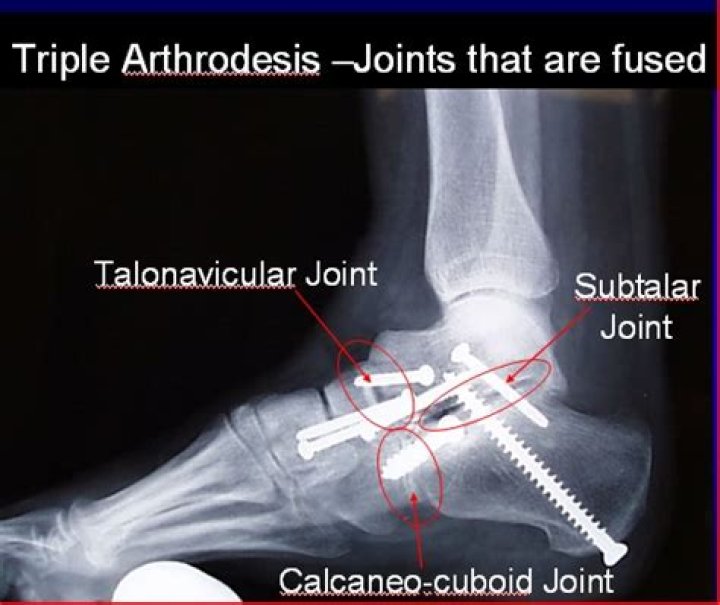

What is a triple arthrodesis of the ankle

A triple arthrodesis is a procedure consisting of the surgical fusion of the talocalcaneal (TC), talonavicular (TN), and calcaneocuboid (CC) joints in the foot. The primary goals of a triple arthrodesis are to relieve pain from arthritic, deformed, or unstable joints.

Most triple arthrodesis procedures are performed by removing all of the cartilage from the three joints involved—that is, the talocalcaneal (TC) joint (also referred to as the subtalar joint), the talonavicular (TN) joint, and the calcaneocuboid (CC) joint—and fusing them with bone-to-bone contact.

The term “triple” arthrodesis refers to a fusion procedure of three joints of the hindfoot and midfoot, the subtalar joint (talus and calcaneus), the talonavicular joint, and the calcaneocuboid joint.

A triple arthrodesis is a fusion in the hindfoot (back of the foot) used to treat many types of painful foot deformities. This procedure fuses the joints under the ankle that allow the foot to move from side to side. These joints are the talonavicular, subtalar, and calcaneocuboid.